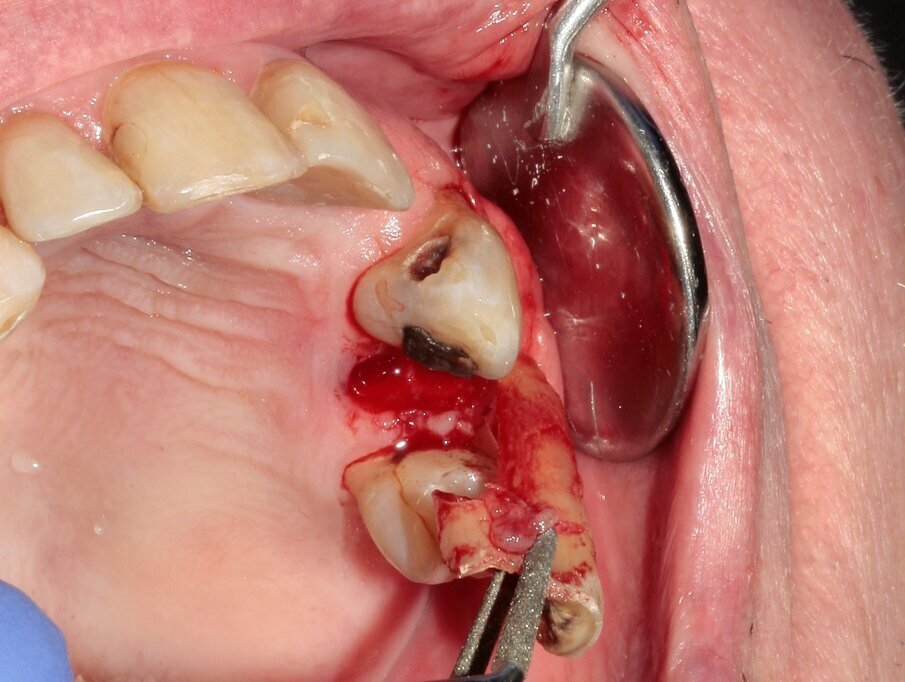

Fig. 8: The tooth was removed with the help of diamond tweezers.

Fig. 9: During luxation, the palatal root was partially fractured while in the alveolus.

Figs. 10–12: The fractured root was carefully luxated with Luxator P1 and Luxator L3S.

Figs. 13–15: The remains of the root were removed with the help of diamond tweezers.

By means of a gentle extraction technique, we managed to preserve the interradicular septum. Luxator P4, with its extremely sharp dual-edge blade, was used at the beginning, followed by Luxator P1 once some space had been created. Although the blades of these sophisticated instruments are reinforced with a titanium coating, they should only be used to cut the periodontal ligament and never to elevate the tooth.